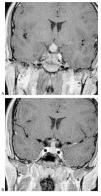

Casos en imagen 4

Case 4

Figuras (3)